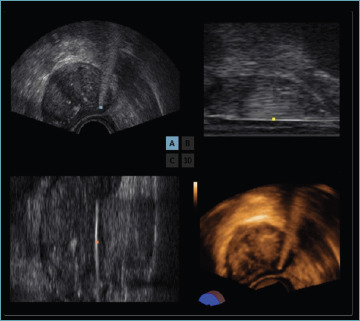

Multiparametric magnetic resonance imaging (mpMRI) has improved systematic prostate biopsy procedures in the diagnosis of clinically significant prostate cancer (csPCa) by reducing the number of unnecessary biopsies; numerous level one evidence studies have confirmed the accuracy of MRI-targeted biopsy, but, still today, systematic prostate biopsy is recommended to reduce the 15-20% false negative rate of mpMRI. New advanced imaging has been proposed to detect suspicious lesions and perform targeted biopsies especially when mpMRI cannot be performed. Transrectal ultrasound (TRUS) modalities are emerging as methods with greater sensitivity and specificity for the detection of PCa compared to the traditional TRUS; these techniques include elastography and contrast-enhanced ultrasound, as well as improved B-mode and Doppler techniques. These modalities can be combined to define a novel ultrasound approach: multiparametric ultrasound (mpUS). More recently, micro-ultrasound (MicroUS) and prostate-specific membrane antigen (PSMA) positron emission tomography/computed tomography (PET/CT) have demonstrated to be sensitive for the detection of primary prostatic lesions resulting highly correlated with the aggressiveness of the primary prostatic tumor. In parallel, artificial intelligence is advancing and is set out to deeply change both radiology and pathology. In this study we address the role, advantages and shortcomings of novel imaging techniques for Pca, and discuss future directions including the applications of artificial intelligence-based techniques to imaging as well as histology. The significance of these findings for the practicing pathologist is discussed.

Abstract Image